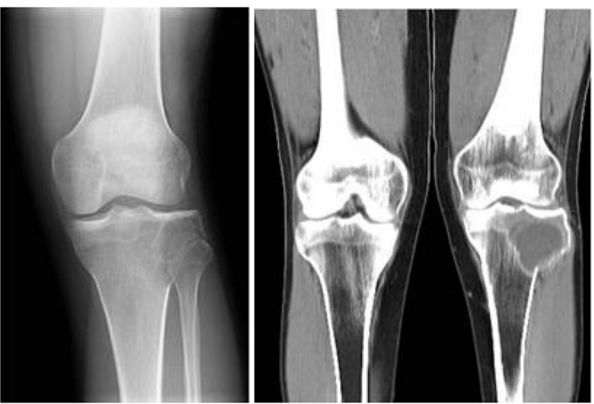

72.23歲男性,無特殊病史。因左膝扭傷,意外發現骨骺(epiphysis)腫瘤。附圖為X光攝影及 電腦斷層影像,最可能的診斷為何:

(A)fibrous dysplasia (B)giant cell tumor (C)osteogenic sarcoma (D)bone metastasis